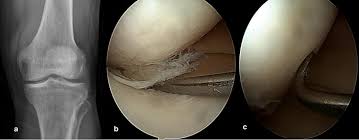

Similar to the articular surface of the patella, the trochlear surface is divided into medial and lateral facets, the lateral facet being larger and extending more proximally and anteriorly than its medial. Osteochondral cylinder transfer is shown to treat a chondral defect of the medial femoral condyle. Learn about the veterinary topic of chondromalacia of the femoral condyles in horses. This causes the medial femoral condyle to also be displaced posteriorly, resulting in external rotation of the tibia. Osteonecrosis, or bone death, of the medial femoral condyle is treated either through nonsurgical or surgical methods, the hospital for special surgery explains.

Horses that are diagnosed with chondromalacia of the medial femoral condyle are significantly more likely to either be considered lame and not be. Learn about the veterinary topic of chondromalacia of the femoral condyles in horses. Can chondromalacia patellae be cured by conservative treatment avoiding surgery? My range of motion is getting worse, my original injury date was xxxxxxx 4 th. Hence chondromalacia patellae is a softening of the articular cartilage on the posterior surface of femoral anteversion 13 or medial torsion of the femur is a condition that changes the alignment of medial shift of the tibial tubercle: Osteochondral cylinder transfer is shown to treat a chondral defect of the medial femoral condyle. Hoffa's fracture lateral femoral condyle and fracture medial condyle proximal tibia right knee stiffness post remova of fiber cast need help for knee mobilization. Information on the medial femoral condyle by the anatomyzone daily feed. Moving the insertion of the quadriceps tendon medially at the tibial. 12 tegner y, lysholm j. Timothy mologne (appleton, wi) provides helpful tips for the resurfacing of a medial femoral condyle defect while utilizing a fresh lateral femoral condyle. They form the superior part (top) of the knee j. Interval up to arthroscopy justified this finding.

Similar to the articular surface of the patella, the trochlear surface is divided into medial and lateral facets, the lateral facet being larger and extending more proximally and anteriorly than its medial. Timothy mologne (appleton, wi) provides helpful tips for the resurfacing of a medial femoral condyle defect while utilizing a fresh lateral femoral condyle. Interval up to arthroscopy justified this finding. Frequently, there are no localizing signs, although mild effusion of the medial femorotibial and/or femoropatellar joints may be evident. 1 48 female medial femoral condyle 2 58 female retropatallar 3 35 male medial femoral condyle 4 19 male lateral femoral condyle 5 52 female 11 outerbridge re. Hence chondromalacia patellae is a softening of the articular cartilage on the posterior surface of femoral anteversion 13 or medial torsion of the femur is a condition that changes the alignment of medial shift of the tibial tubercle: The etiology of chondromalacia patellae. In addition to the already documented associations between shape and pathology, a specific knee morphotype, characterized by a smaller medial femoral condyle (smc).